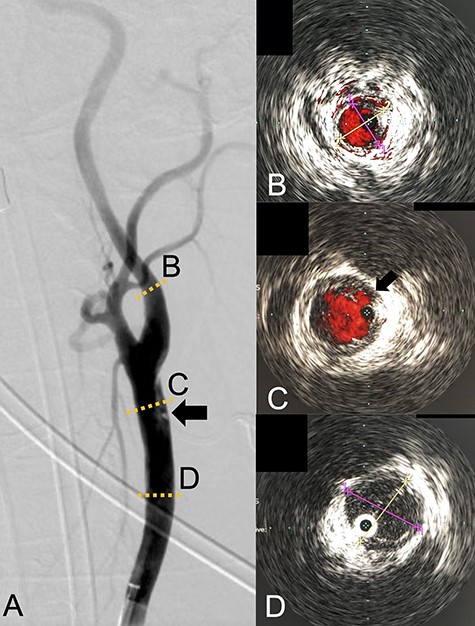

We performed CAS and started dual antiplatelet therapy 27 days after stroke onset to prevent further dissection and cerebral infarction recurrence. The dissection started 1.5-cm below the carotid bifurcation (Fig. 3A). An 8 fr guiding catheter (FlowGate2 Balloon Guide Catheter, Stryker, Fremont, CA, USA) was positioned at the proximal portion of the left CCA with a micro-guidewire (ASAHI CHIKAI Black, Asahi-Intecc, Nagoya, Aichi, Japan) crossing the dissected lesion. A distal protection device (SpiderFx Embolic Protection Device, Medtronic, Minneapolis, MN, USA) was deployed at the petrous portion of the ICA. IVUS was first advanced into the petrous ICA, and vessel wall imaging was performed by slowly withdrawing the device. IVUS imaging confirmed the existence of the dissection’s pseudo-lumen starting 1-cm proximal to the carotid bifurcation (Fig. 3C). IVUS provided the ICA and CCA diameters, which helped decide the most suitable stent (Fig. 3B and C). To adequately cover the dissection lesion, we placed two opened cell stents (Protégé, Medtronic, Minneapolis, MN, USA); one was an 8–6-mm tapered model with a length of 40 mm to cover the lesion from the distal CCA end to the proximal portion of ICA. Another was a 10-mm straight model with a length of 40 mm covering the CCA. Post-dilation was performed SterlingTM Balloon Dilation Catheter (Boston Scientific, Natick, MA, USA) with 5 × 20 mm covering both stents’ edges. The final angiography showed successful treatment with a smooth intra-arterial lumen (Fig. 4A). IVUS imaging showed sufficient stent coverage of the entire dissection lesion. It also confirmed a good expansion of the stent to the dissection area’s arterial wall with no plaque protruding the stents (Fig. 4B).

Angiography after stent placement showed favorable patency of the carotid artery with a smooth intra-arterial lumen (A). IVUS performed after stenting confirmed an excellent expansion of the stent to the dissection lesion’s arterial wall with no plaque protruding the stents (B).

We would further like to note the usefulness of IVUS in this particular case. IVUS clearly visualized both the dissection’s entry point and the blood flow from true- to pseudo-lumen, the information of which is essential for treatment strategy planning. IVUS also provided helpful information to assess the stent’s coverage (Fig. 3). IVUS allowed us to predict the entire length of the arterial dissection before stent deployment [11]. Furthermore, IVUS provided important information for stent-size selection. Although the pseudo-lumen caused by the dissection made it difficult for us to precisely measure the true lumen diameter, IVUS allowed us to measure the diameter of the true lumen of the dissected artery, and we were able to select the appropriate stent for treatment. It also provided helpful information that proper stent apposition was established even after the stent deployment and post-balloon dilation, which indicated no additional angioplasty was necessary.